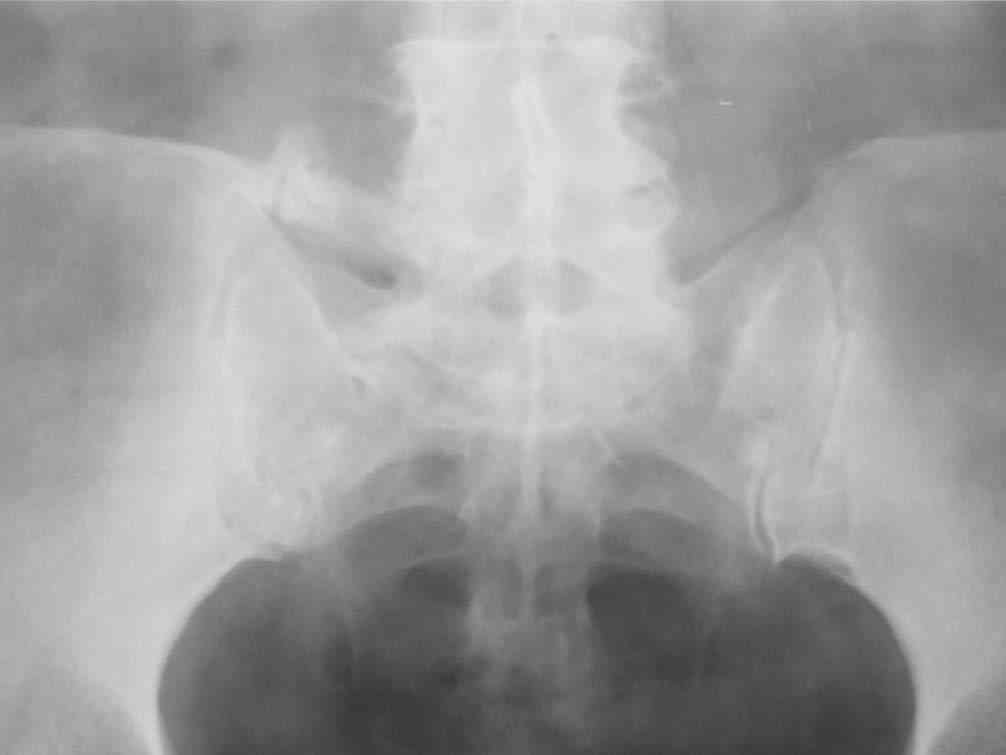

Если позволите, некоторые теоретические соображения по результатам и показаниям. Сегодня все знают как оперировать позвоночник по поводу любых "напастей". Когда после операции боли остаются приходит время вспомнить о том, что морфологический субстрат боли при полисегментарной саногенетической реакции патологического типа, каким является остеохондроз и другие спондилогенные изменения дегенеративно-дистрофического характера, точно установить, как правило, невозможно. Аномалиям развития здесь особенно не повезло. Например, если у пациента протрузии на нескольких уровнях, дегенеративный стеноз и сакрализация - лечат сакрализацию т.к. она "режет глаз" специалисту. Соответственно и эффект от вмешательства на уровне "не навредили". Специальные методы исследования мало что дают в этом плане, а МРТ, вообще, годится только для обоснования необходимости операции при разборе жалобы. Поэтому вначале рекомендую лечебно-диагностические тест-блокады. Если эпидуральная по Катлену через день (результат оценивать после 3-5 блокад) снимает жалобы - оперировать не стоит. Если локальная боль остается - прицельную паравертебральную в зону неоартроза - исчезновение боли показание не к операции, а к повторному курсу через 3-6 мес. Стойкий локальный монолатеральный болевой синдром - повод задуматься об операции. Но, как правило, она должна быть более обширной чем просто резекция поперечного отростка и санировать и другие проблемы. "Золотой стандарт" тут пока передне-задняя фиксация в различных ее вариантах в зависимости от конкретного случая. Попытки "располовинить" спондилодез в отношении чистой изолированной транспедикулярной фиксации в пятилетнем наблюдении не выдерживают критики. Передняя изолированная фиксация пластинами с аутокостным спондилодезом дает хорошие результаты (пример на фото 4)

при условии дополнения задним релизом для декомпрессии сосудисто-нервных образований ( ну а тогда почему уже и конструкцию сзади не поставить? фото 5).